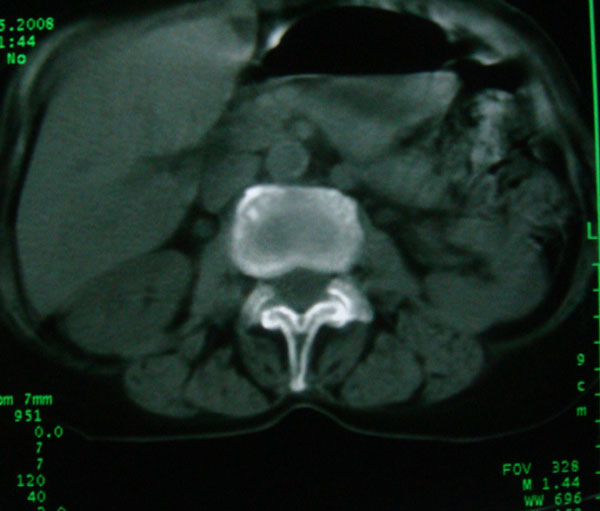

以下是引用卜一在2008-5-24 6:33:00的发言:[br]骨岛!建议定期复查!

以下是引用panyishengct在2008-5-23 23:19:00的发言:[br]骨岛,不排除成骨性转移瘤.

以下是引用pujunzhi在2008-5-24 1:02:00的发言:[br]支持2楼 骨岛,不排除成骨性转移瘤

以下是引用gaoshengjiang在2008-5-24 8:25:00的发言:[br]骨岛,不排除成骨性转移瘤. [br] [br]

以下是引用zjzjr在2008-5-24 14:55:00的发言:[br]骨岛!建议定期复查!